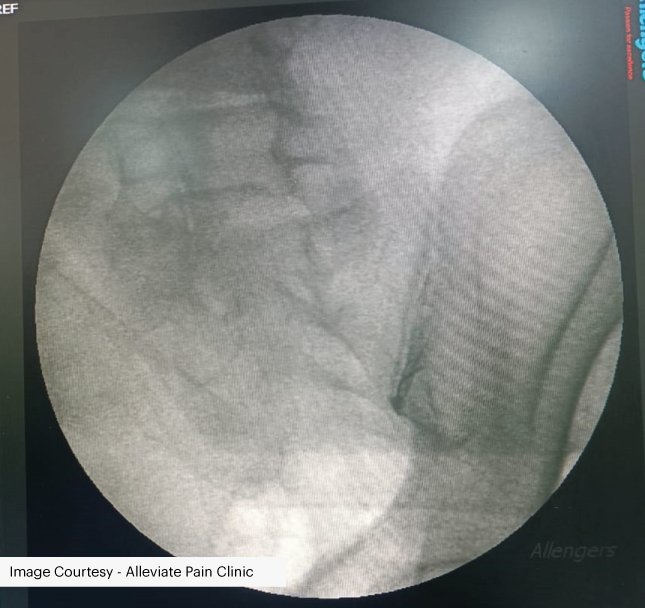

SUCCESS AT ALLEVIATE